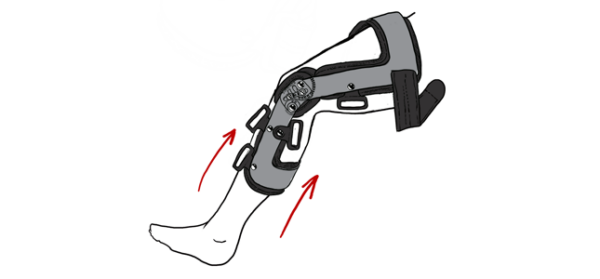

9. Wyprostować kończynę i dopiąć tylny pas łydkowy oznaczony numerem (5).

1. Orteza została wyposażona w system miękkich osłon antypoślizgowych, posiadają one funkcję samoszczepną i należy je ustawić w taki sposób aby ich środek zawsze znajdował się w osi kończyny dolnej. Jeżeli zachodzi uzasadniona potrzeba osłony te można przyciąć z długości. Przycięcie takie nie powoduje uszkodzenia osłony i nie ma potrzeby dodatkowego jej zabezpieczania.

2. Pasy obwodowe ortezy RAPTOR 2RA posiadają funkcję samoszczepną i są wyposażone w zapięcia rzepowe. Pasy posiadają również wewnętrzne zapięcie regulacyjne, które pozwala na ustawienie właściwej dla danego pacjenta długości obwodowej pasa.

Funkcjonalna orteza stawu kolanowego RAPTOR/2RA to doskonała opcja w przypadku uszkodzenia PCL jak i profilaktyki tego urazu. Orteza została wykonana z wyjątkowo mocnej przednio-tylna ramy z lekkiego aluminium 6061 T6 mającego zastosowanie w lotnictwie. Takie rozwiązanie gwarantuje najlepszą stabilizację wśród ortez dostępnych na rynku. Dodatkowo w celu lepszego zabezpieczenia ortezy przed wilgocią, rama została pokryta na gorąco trwałą powłoką proszkową, co powoduje, iż orteza jest obojętna na działanie wody oraz potu pacjenta. W ortezie zamontowano pięć pasów stabilizujących, wyposażonych w poduszki antymigracyjne z silikonem, stanowiące dodatkowe wsparcie i zapobiegające przesuwaniu się ortezy na kończynie. Orteza została wykonana z surowca Active3D™. Wewnętrzna miękka wyściółka ramy została wykonana z pianki EVA posiadającej właściwości wodoodporne i odciążające.

Orteza kolana RAPTOR/2RA stabilizuje staw w płaszczyźnie strzałkowej i czołowej. Orteza RAPTOR/2RA posiada 4-punktowy system podparcia, który doskonale stabilizuje i odciąża staw kolanowy. W przypadku uszkodzonego więzadła krzyżowego tylnego (PCL), kość piszczelowa ma tendencję do nadmiernego przemieszczania się w kierunku tylnym względem kości udowej. Konstrukcja przednio-tylna ortezy pozwala na zabezpieczenie piszczeli i ustawienie jej w osi stawu kolanowego.